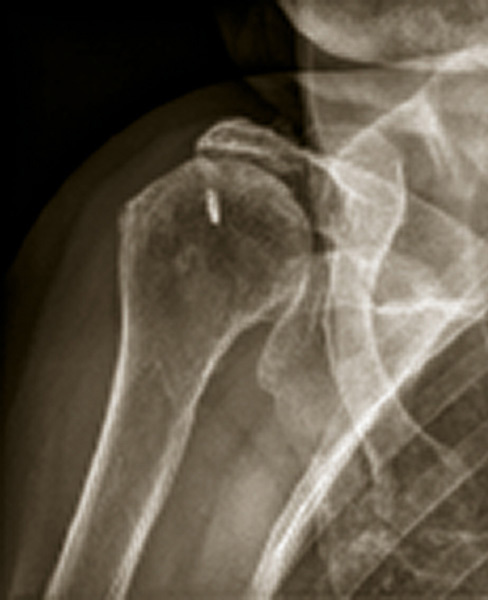

Omarthrose excentrée

Radiolographie d'une marthrose excentrée